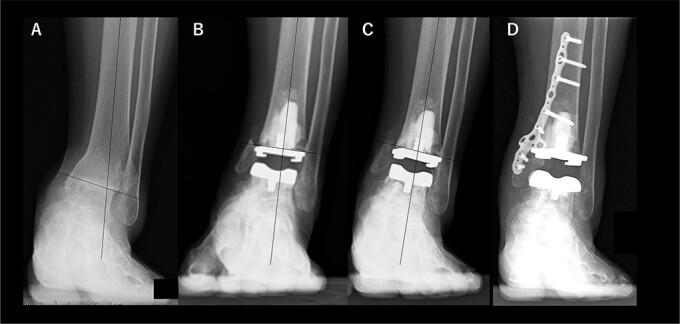

Of the three ankles after total ankle arthroplasty (TAA) with medial malleolar osteotomy for severe varus deformity (talar varus tilt >10°), two failed in varus migration of the tibial component. In these two cases, tibial osteotomy was performed with varus alignment of 5°and 2°, and with medially shifted placement of tibial component, while one ankle showed no migratoin of prostheses after 5 years, even with nonunion. In this case, tibial osteotomy was performed with a valgus alignment of 4°. Internal fixation after medial malleolar osteotomy should be done for severe varus cases. Medially shifted placement of tibial component should be avoided. Fortunately, the failure did not occur in a case of valgus of the distal tibia. Valgus tibial osteotomy might help to reduce the collision of the talus against the medial malleolus.

在因严重内翻畸形(距骨内翻倾斜>10°)行内踝截骨的全踝关节置换术(TAA)后的三个踝关节中,有两个出现胫骨部件内翻移位失败。在这两个病例中,胫骨截骨时分别采用了5°和2°的内翻对线,且胫骨部件向内侧移位放置,而另一个踝关节在5年后假体未出现移位,即使存在骨不连。在这个病例中,胫骨截骨采用了4°的外翻对线。对于严重内翻病例,内踝截骨后应进行内固定。应避免胫骨部件向内侧移位放置。幸运的是,胫骨远端外翻的病例未出现失败情况。胫骨外翻截骨可能有助于减少距骨与内踝的碰撞。